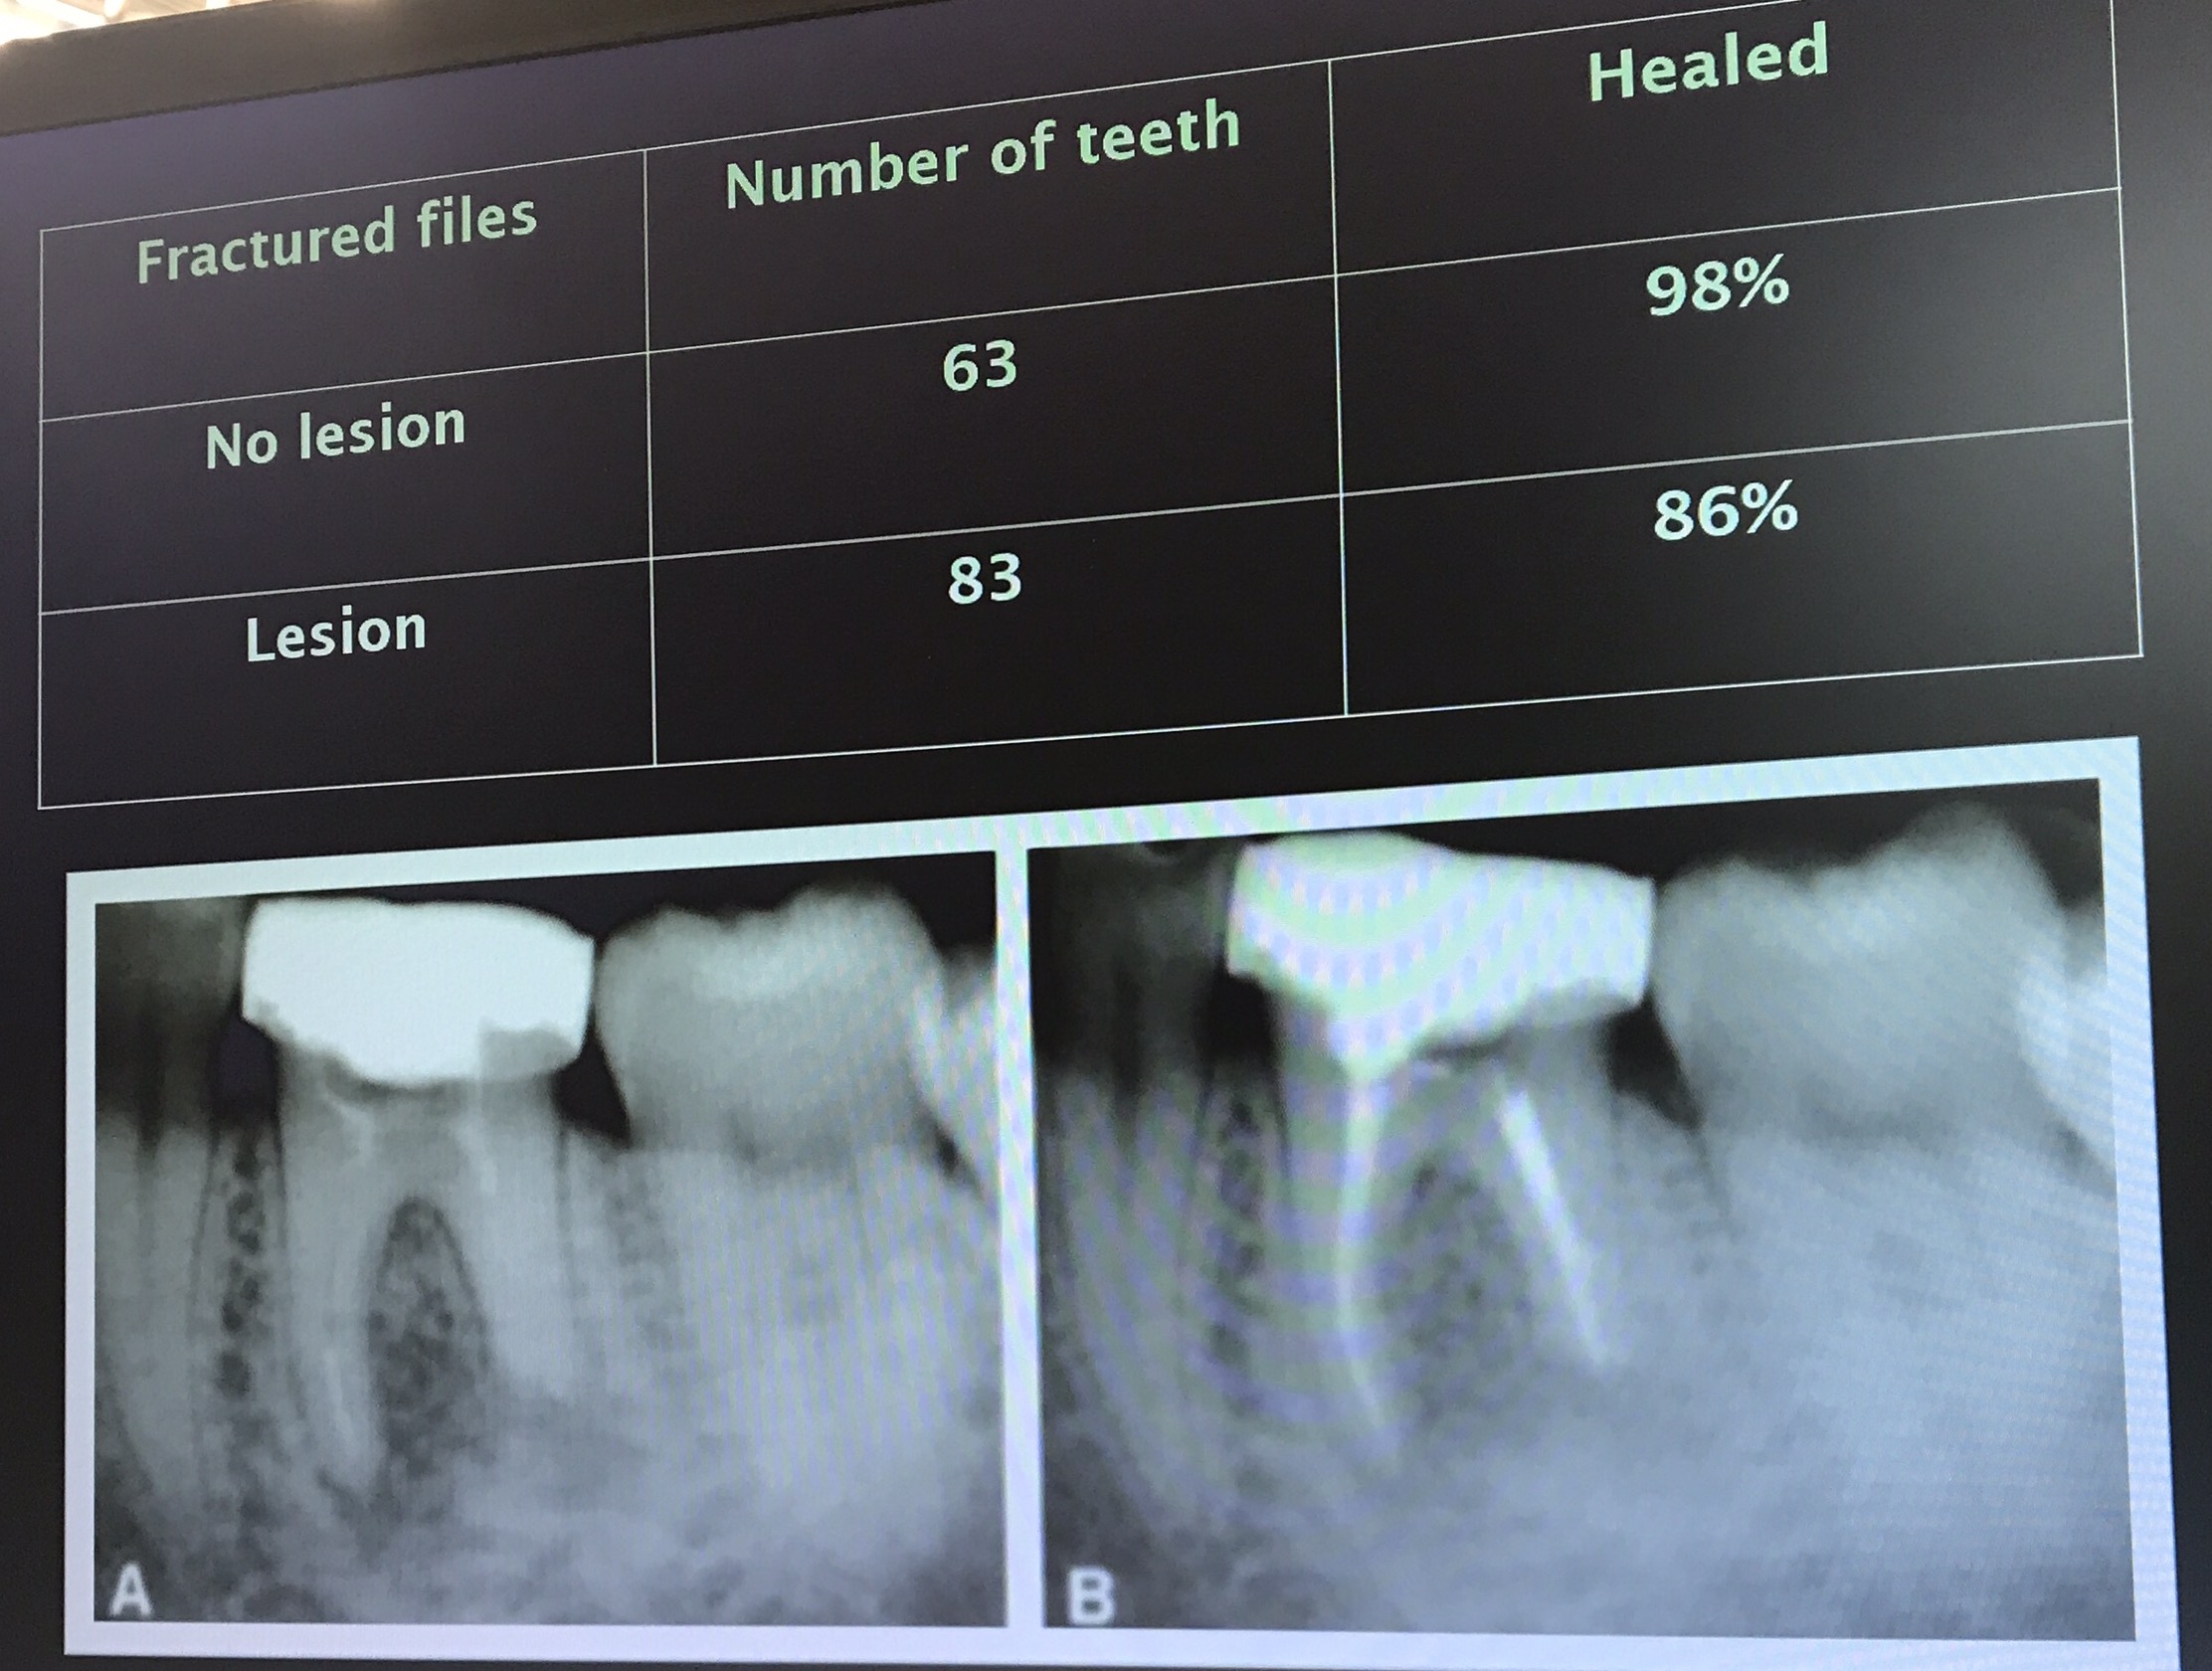

Lecture เรื่อง remove เครื่องมือที่ broken สั้นมาก

อุบัติการค่อนข้าง vary

Paper นี้บอก success rate ไม่ต่างกันเลย

แต่พบว่า ในฟันที่มี lesion success จะ drop ลงประมาณ 20%

ถ้าเครื่องมือหักเลย curve การรื้อออกจะยากมาก